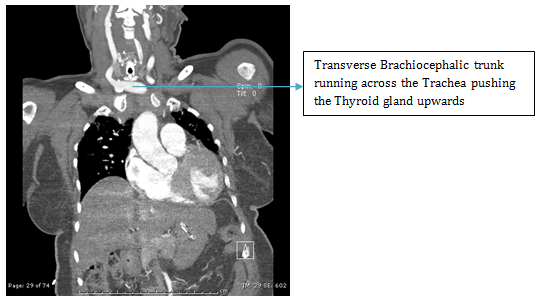

ENT referral was sought and a colour Doppler was advised which showed an abnormal large artery in running across in front of the Trachea. A CT angiography was then done which revealed anomalous Brachiocephalic trunk running from left to right across in front of the trachea which had pushed the thyroid gland to the level of Cricoid cartilage (Figures 1-4).

Figure 1 Angiogram.

Figure 2 Angiogram.

Figure 3 Angiogram

Figure 4 VRT, CT Angiography

Literature was searched for this anomaly and it was found to be a rare anomaly (Beautiful description in an anatomy journal).4 The challenges were two: first, the surgical difficulty in view of the horizontally running large vessel in front of the trachea just 1cm below the Cricoid cartilage and second, the risk of post operative hemorrhage due to the vessel hitting against the Tracheostomy tube due to pounding pulsations, movement of the tube due to mechanical ventilation, frequent handling for suctioning and dressing and neck movements.5-7